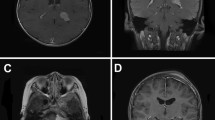

On magnetic resonance imaging (MRI), meningiomas are iso-hypointense on T1-weighted imaging and hyperintense on T2-weighted imaging. Marked gadolinium enhancement is seen (Fig. 4). MRI is superior to computed tomography (CT) in providing detailed information about the tumor. MRI enables better delineation of tumor borders, associated edema, interfaces, and cystic areas. The “dural tail sign” can occur as a characteristic feature, although it is not present in every case, and reflects neoplastic dural infiltration or reactive vascularity or both, draining into the adjacent dura. CT appearances are of a hyperdense mass with variable calcification, edema, and hyperostosis. CT is more effective than MRI at demonstrating the effects on adjacent bone [63]. On CT, meningiomas enhance homogeneously and diffusely after contrast [60, 64–66]. Several studies have looked at the correlation between MRI signal changes, diffusion-weighted MR, MR spectroscopy, and positron emission tomography with histopathology in adult meningiomas. Whereas some studies have revealed a correlation between imaging features and tumor grade, others have not. Consequently, no clear consensus has been reached [63, 67–73].

Meningiomas can also have a cystic component (Fig. 4). Pediatric meningiomas are more likely to be cystic than their adult counterparts (24% vs. 2–4%) [74]. Four types of cyst have been described in meningiomas. The cyst may be intra-tumoral, either in the center (type I) or on the periphery (type II), or peri-tumoral, either within the brain substance (type III) or at the brain-tumor interface (type IV) [60]. Type II cysts are the most frequent in pediatric meningiomas [75]. Cysts form after necrosis, degeneration, and hemorrhage. Glial response or arachnoid reaction may also contribute [1]. Pediatric meningiomas have been noted to be larger in size compared to adult tumors [64]. Multiple meningioma at presentation is less common in children than adults (2.5% vs. 8–9%) [76]. Lack of dural attachment is rare in adults but can be found in up to 13–30% of childhood cases [77]. Calcification is another finding that can be present on imaging (Fig. 5) and is more readily seen on CT than MRI.